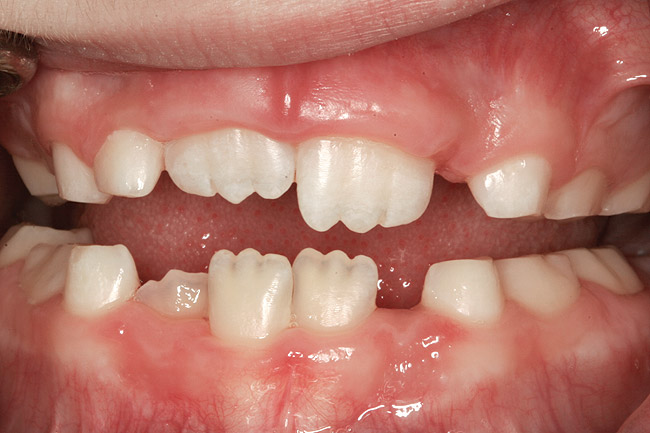

(3.) Three-year-old with a history of snoring, bruxing, and thumbsucking. Her father and brother were both diagnosed with OSA.

Figure 3

(4.) Patient presents bilateral crossbite and significant attrition. Father assists in retraction.

Figure 4